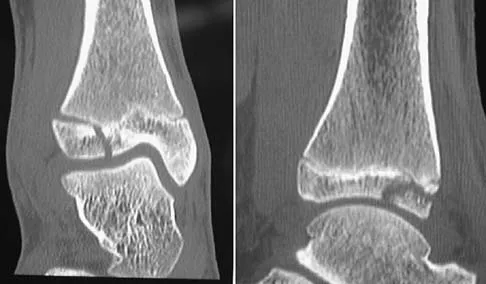

What is the primary mechanism of injury for the fracture shown in Figures 33a and 33b?

Detailed Explanation